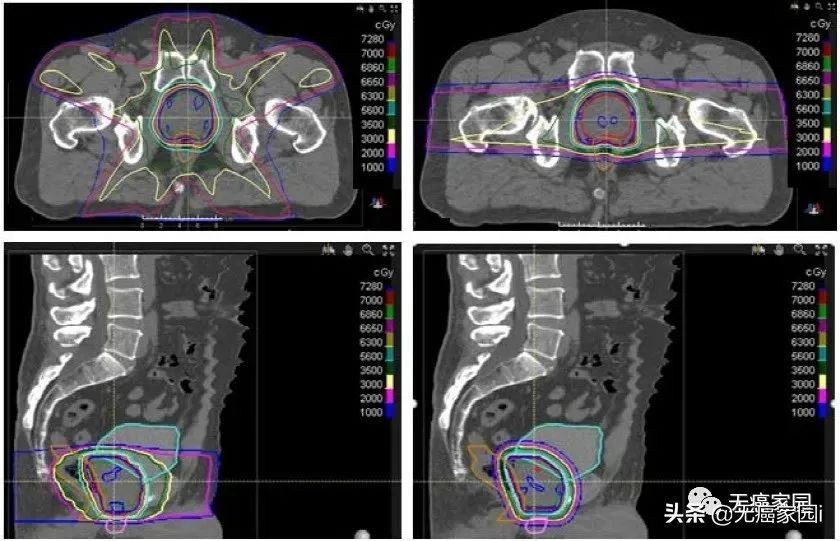

Chera等人对15例需要盆腔淋巴结照射的高危前列腺癌患者的IMRT和DSPT计划进行了比较。临床靶区体积(CTVs)包括盆腔淋巴结、前列腺和近端精囊。前列腺和近端精囊CTV与淋巴结CTV序贯照射,分别为46 Gy,每次2 Gy。将前列腺和近端精囊CTV推量32 Gy,总剂量78 Gy。与IMRT相比,DSPT计划显著减少了接受5~40 Gy的直肠体积,从71%减少至53%。质子治疗也显著减少了过量照射的膀胱V5~V40 GyRBE,从63%减少至40%。

IMRT与DSPT前列腺癌治疗的比较。质子治疗计划减少了膀胱、直肠和阴茎球的辐射剂量,但增加了股骨头的剂量。两个计划与处方等剂量线的适形性相似。